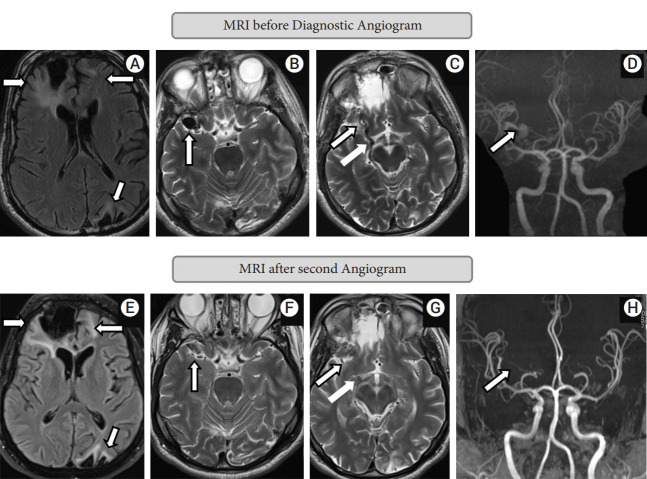

Intracranial non-galenic pial arteriovenous fistula (PAVF) is an extremely rare vascular malformation, where one or more pial arteries feeds directly into a cortical vein without any intervening nidus. Though occasionally they can be asymptomatic, neurological symptoms such as headache, seizure, or focal neurological deficit are more common presenting features. Life threatening or fatal hemorrhage is not uncommon, hence needed to be treated more often than not. Spontaneous occlusion of PAVF is reported only four times before. We report a 49-year-old gentleman, who was diagnosed to have a PAVF, possibly secondary to trauma. He presented 5 months and 22 days from initial digital subtraction angiography (DSA) for treatment, and follow-up angiogram showed complete obliteration. He denied any significant event, medication or alternate treatment during this period. His clinical symptoms were stable as well. We postulate iodinated contrast medium induced vasculopathy as a possible cause, which has been described for other vascular pathologies, but never for PAVF.